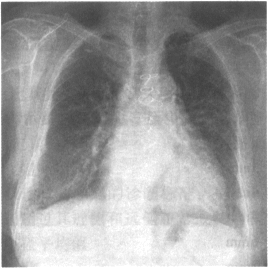

女性,46岁。呼吸困难入院,胸部X线平片如下图,右侧肋膈角区垂直于胸壁内侧面的线状影为

题型: 单选题 分类: 392中级急诊医学

• A.Kerley A线

• B.Kerley B线

• C.Kerley C线

• D.盘状肺不张

• E.胸腔积液